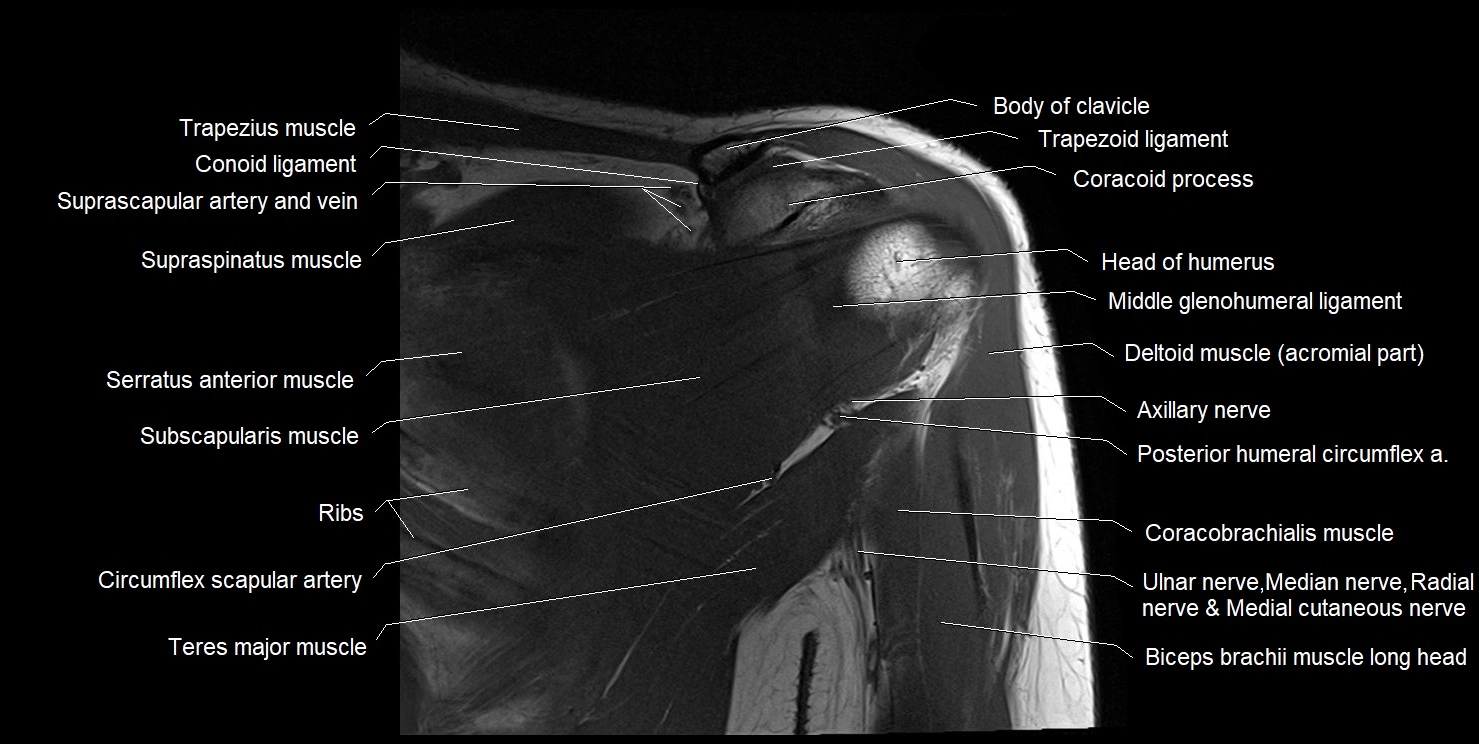

CT image

image